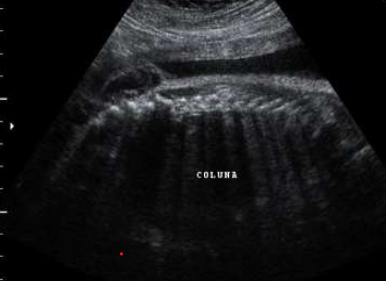

Paciente 24 anos, secundigesta, apresentando idade gestacional de 23 semanas, gestação não planejada, encaminhada para avaliação morfológica do segundo trimestre.

Após analisar as imagens abaixo, quais os sinais ecográficos encontrados e qual a hipótese diagnóstica?